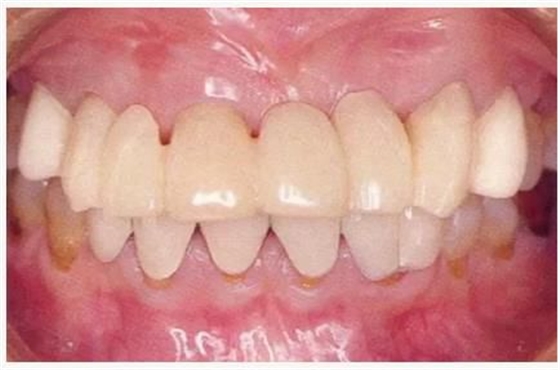

圖6-9 牙周外科治療5個(gè)月后,最終取模前的狀態(tài)?;乐車@得了充足的附著齦。

圖6-10 佩戴最終修復(fù)體時(shí)的X光照片。